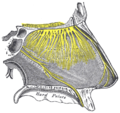

التعصيب

- الحس العام: عن طريق فروع من أول فرعين للعصب مثلث التوائم (العيني والفكي العلوي). فالأجزاء الأمامية لجوف الأنف يتم تعصيبها بواسطة العصب الغربالي الأمامي فرع العصب الأنفي الهدبي (الذي بدوره يتفرع من العصب العيني)، أما الأجزاء الخلفية من جوف الأنف يتم تعصيبها عبر فروع للعقدة الجناحية الحنكية والتي تصلها ألياف من العصب الفكي العلوي.

- حس الشم: عن طريق ألياف العصب الشمي التي تعبر الصفيحة المصفوية.[1]